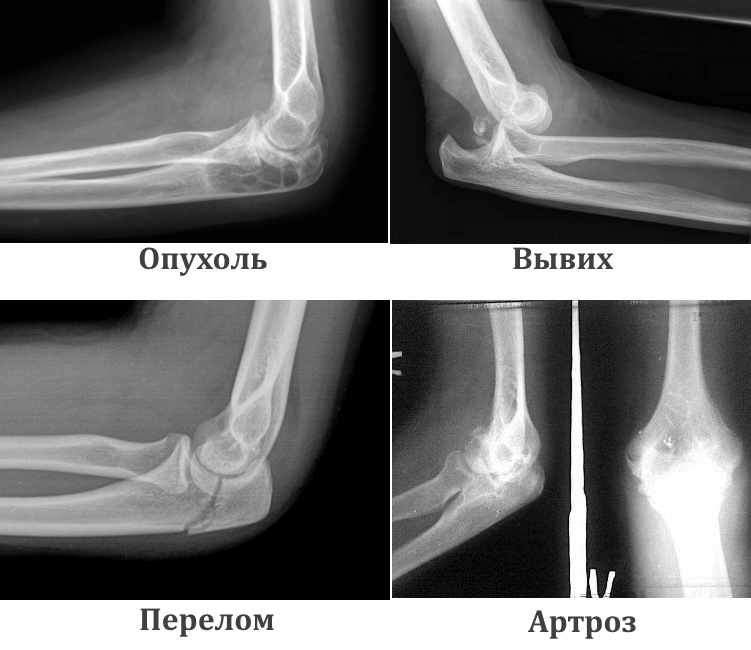

На фото ниже представлены различные виды патологий локтевого сустава.

Рассмотрим характерные признаки отклонений, которые можно обнаружить с помощью рентгенологического исследования.

| Перелом | Позволяет определить тип перелома, его локализацию и степень сложности. | Кости отображаются как белые продолговатые структуры. Переломы выглядят как затемненные линии на костях. По типу линий различают поперечные, косые и винтообразные переломы. Наличие нескольких линий указывает на осколки. |

| Вывих | Выглядит как смещение предплечья относительно плечевой кости в местах соединения. | На снимке можно увидеть тип вывиха: наружный или внутренний. |

| Артроз и артрит | Обнаруживаются разрушения хрящевой ткани, изменения формы и размеров костей, образующих сустав. | Суставная щель может быть почти незаметна из-за разрастания костной ткани. Наблюдается воспаление синовиальной оболочки и ее отечность. Визуально можно заметить аномалии в соединении костей и изменения их структуры. |